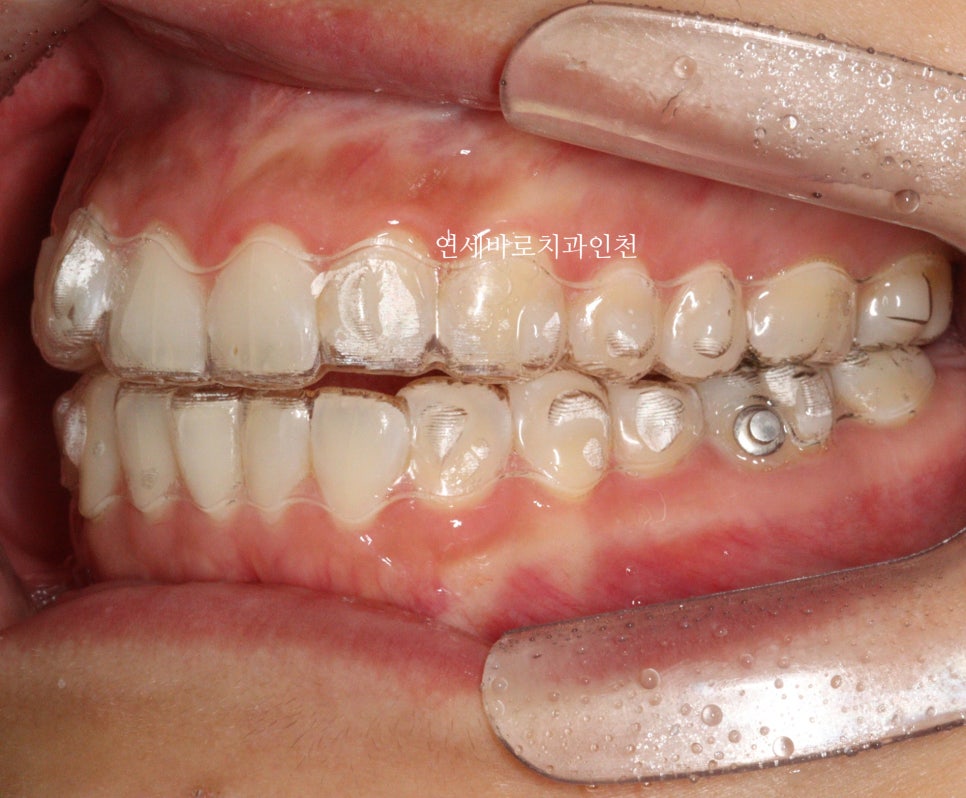

교정이 마무리되고 보면 문제없죠?

이분은 재제작없이 끝냈습니다.

치아의 배열만 하기로 했다면 #인비절라인라이트 도 가능했을 순 있습니다.

하지만 보다 나은 안모의 개선을 위해 comprehensive옵션을 선택, 미니스크류를 동반하여 치료를 마무리한 환자분 입니다.